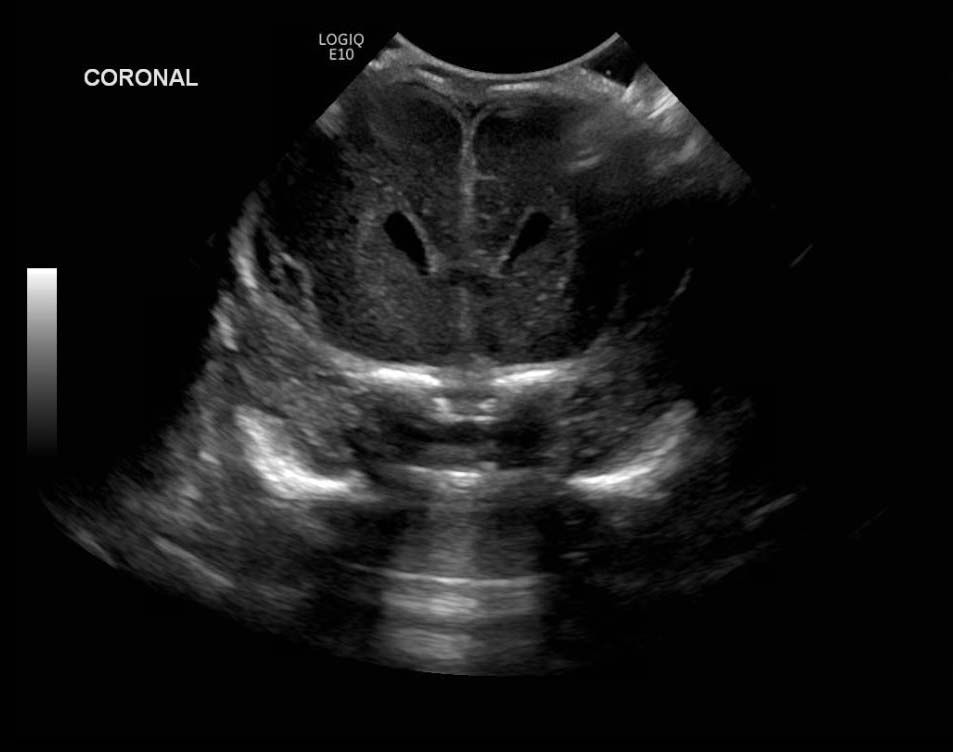

Age: 4 days (born at 24 weeks)

Sex: Male

Indication: Evaluate for germinal matrix hemorrhage

Grade 2 germinal matrix hemorrhage

Sample ReportLeft germinal matrix hemorrhage involving the caudothalamic groove and layering in the occipital horn of the left lateral ventricle without hydrocephalus (grade 2).

No abnormal brain parenchymal echogenicity or extra-axial collections.

Premature sulcation pattern.